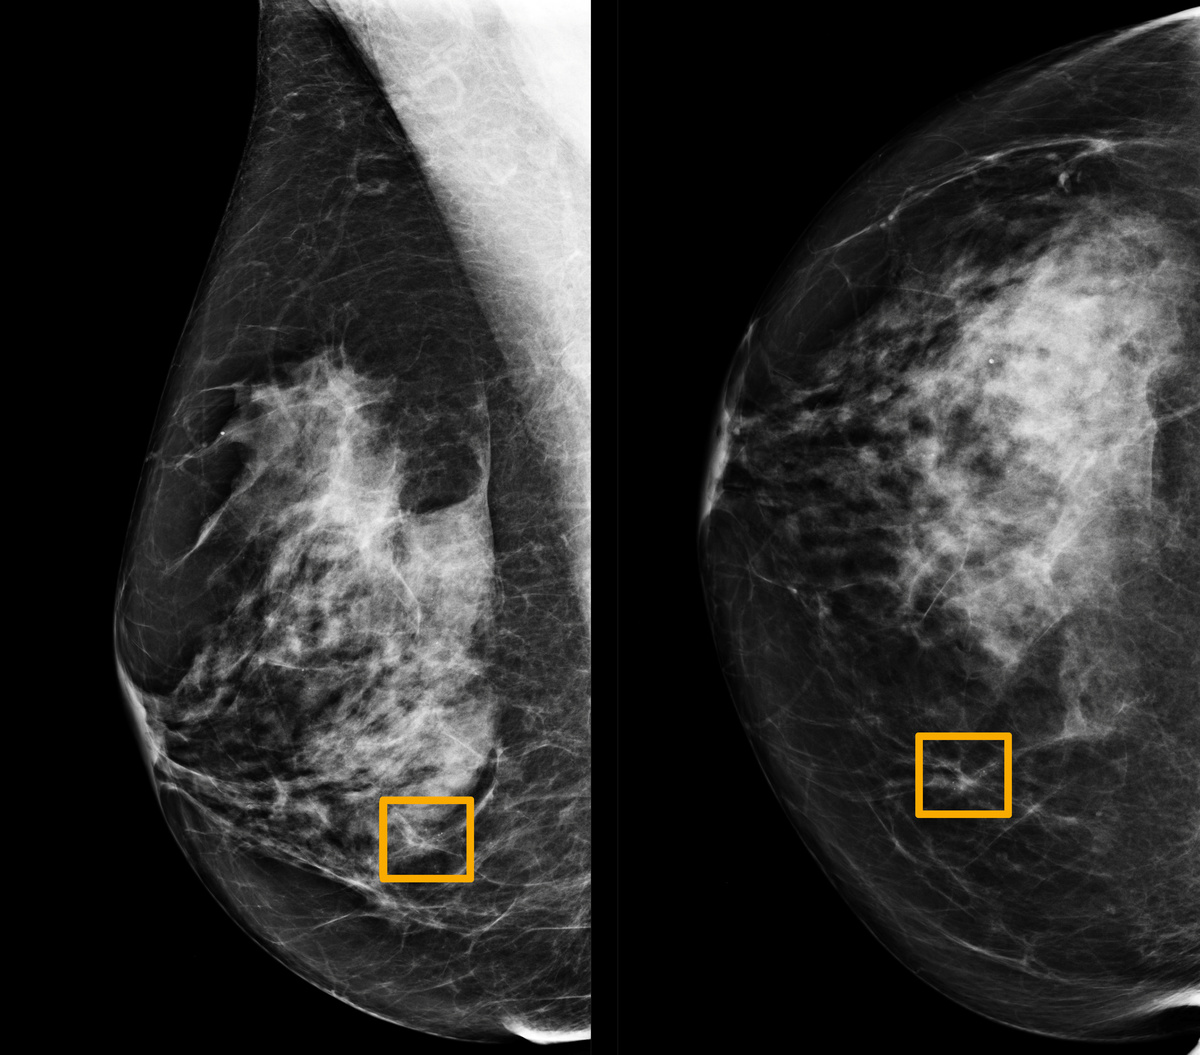

A Google artificial intelligence system proved as good as expert radiologists at detecting which women had breast cancer based on screening mammograms and showed promise at reducing errors, researchers in the United States and Britain reported.

The team, which included researchers at Imperial College London and Britain's National Health Service, trained the system to identify breast cancers on tens of thousands of mammograms.

They then compared the system's performance with the actual results from a set of 25,856 mammograms in the United Kingdom and 3,097 from the United States.

The study showed the AI system could identify cancers with a similar degree of accuracy to expert radiologists, while reducing the number of false positive results by 5.7% in the U.S.-based group and by 1.2% in the British-based group.

It also cut the number of false negatives, where tests are wrongly classified as normal, by 9.4% in the U.S. group, and by 2.7% in the British group.